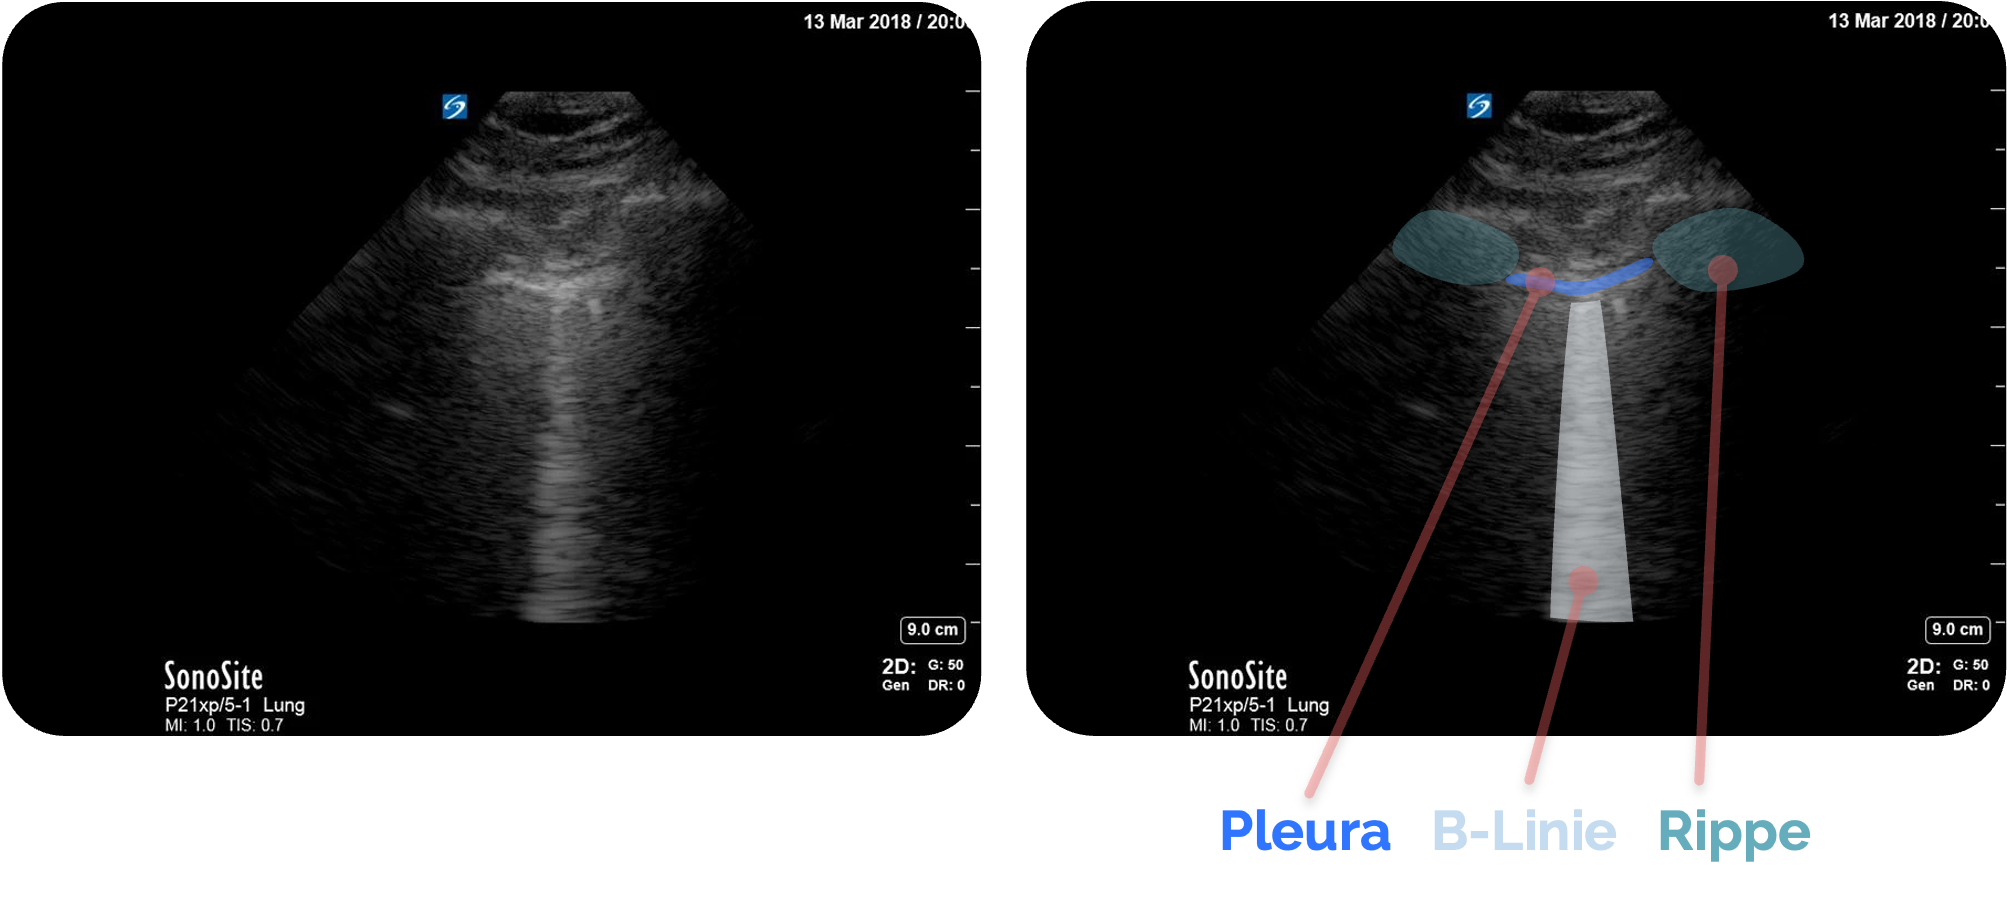

- B-Lines: vertikale, bis zur Bildtiefe reichende Artefakte (kein Hinweis auf Pneumothorax

) (roter Pfeil)

Bildquelle: Figure 2 aus Ketelaars, R., Reijnders, G., van Geffen, GJ. et al. ABCDE of prehospital ultrasonography: a narrative review. Crit Ultrasound J 10, 17 (2018). https://doi.org/10.1186/s13089-018-0099-y. Teilausschnitt des Originalbilds. Der rote Pfeil wurde hinzugefügt.

Normalbefund: B-Linien

B-Linien sind vertikale, echoreiche Artefakte, die von der Pleuralinie ausgehen und sich bis zum unteren Bildrand erstrecken, wobei sie die horizontalen A-Linien überlagern. Sie ähneln in ihrem Aussehen ein wenig einem „Kometenschweif“ und sind in geringer Anzahl physiologisch.

Sie bewegen sich synchron mit dem Lungengleiten und löschen beim Durchtritt die A-Linien aus. Sie entstehen durch Reflexion und Streuung des Schalls an Flüssigkeitsansammlungen in den subpleuralen Septen oder im interstitiellen Gewebe.

Einzelne B-Linien können insbesondere in den basalen Lungenabschnitten, vorkommen, da Flüssigkeit in der Lunge

Mehr als drei B-Linien pro Interkostalraum gelten in der Regel als pathologisch. Entscheidend ist neben der Anzahl auch die Verteilung: diffus

Figure 2 aus Ketelaars, R., Reijnders, G., van Geffen, GJ. et al. ABCDE of prehospital ultrasonography: a narrative review. Crit Ultrasound J 10, 17 (2018). https://doi.org/10.1186/s13089-018-0099-y. Teilausschnitt des Originalbilds. Es wurden die Markierungen und Beschriftungen ergänzt.